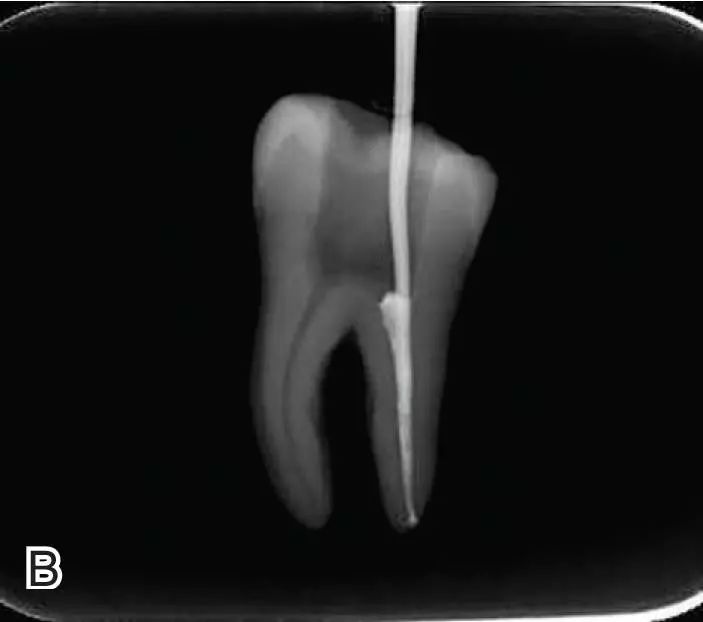

连续波加压

将携热器工作尖向根尖加热加压至距参照点约2 mm处,关闭加热器,保持根向压力,使工作尖前进到参照点处。保持加压状态10秒钟。

退出携热器工作尖

开启加热器1秒钟,迅速退出携热器工作尖,带出中上段多余牙胶尖。用小号垂直加压器向下加压,完成根尖段的充填。